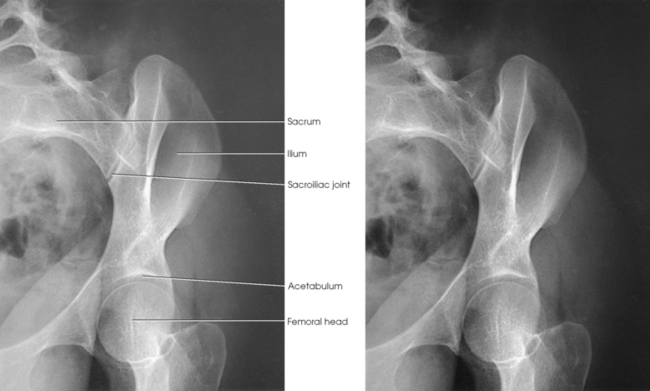

The hip bone consists of the ilium, pubis, and ischium (Figs. 7-1 and 7-2). These three bones join together to form the acetabulum, the cup-shaped socket that receives the head of the femur. The ilium, pubis, and ischium are separated by cartilage in children but become fused into one bone in adults.

The anterior superior iliac spine (ASIS) is an important and frequently used radiographic positioning reference point. The superior margin extending from the ASIS to the posterior superior iliac spine is called the iliac crest. The medial surface of the wing contains the iliac fossa and is separated from the body of the bone by a smooth, arc-shaped ridge, the arcuate line, which forms a part of the circumference of the pelvic brim. The arcuate line passes obliquely, inferiorly, and medially to its junction with the pubis. The inferior and posterior portions of the wing present a large, rough surface—the auricular surface—for articulation with the sacrum. This articular surface and the articular surface of the adjacent sacrum have irregular elevations and depressions that cause a partial interlock of the two bones. The ilium curves inward below this surface, forming the greater sciatic notch.

The right and left ilia articulate with the sacrum posteriorly at the sacroiliac (SI) joints. These two joints angle 25 to 30 degrees relative to the midsagittal plane (see Fig. 7-7, B). The SI articulations are synovial irregular gliding joints. Because the bones of the SI joints interlock, movement is limited or nonexistent.